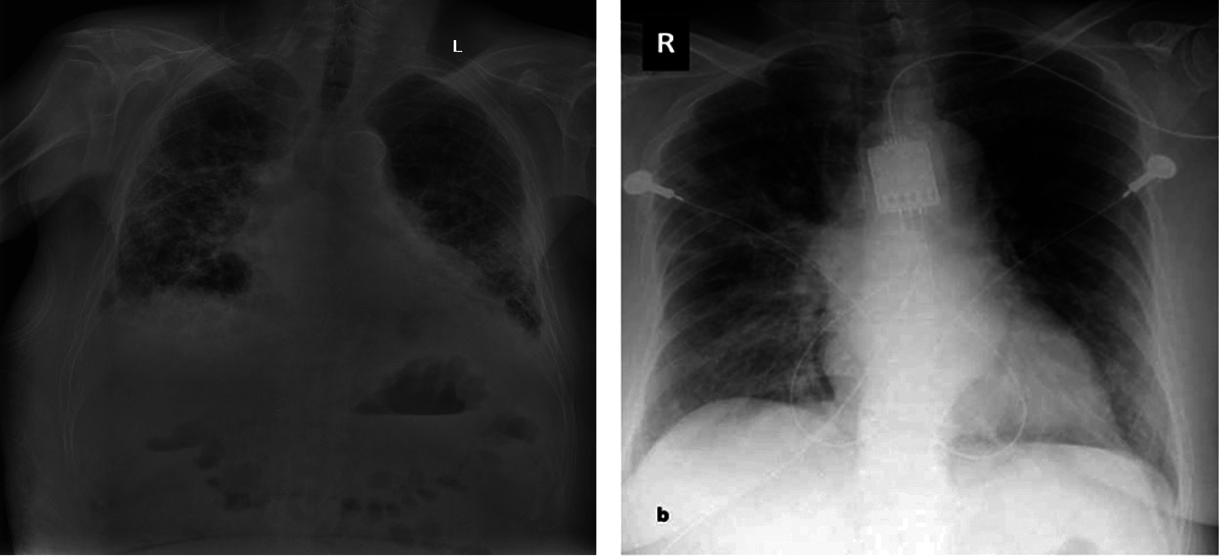

The dataset images, which are divided into two parts. Those are Covid positive and normal CXR images. The images are then converted into (224,224) forms and normalized. At that point, the pictures are rearranged and split into preparing and testing information. Thus, the training part has 60 images and 2 classes. The same testing part has 60 images and 2 classes. There are many possibilities that the same patients’ CXR images are kept in both the training and testing parts. It can be overlapping, but it’s kind of promising that training of the model, which has been examined by testing and validation checking, defines the ability of the trained model. Covid-19 positive and negative patients’ chest X-Ray images below in Figs. 5 and 6.

Figure 5: Covid-19 positive patient CXR pictures

Figure 6: Covid-19 negative patient CXR pictures

Here are 4 images from the dataset which have been taken from the Kaggle dataset. Covid and Normal. The first dataset was distributed in 2018, and from that point forward, around 100 exploration articles have 121 been distributed so far, including its example. The benchmark paper by Kermany et al. reports 122 claims a grouping exactness of 92.8 percent while utilizing the Inception V3 architecture (pre-prepared for the 123 ImageNet datasets) to recognize Normal and COVID tests. When it came to recognizing normal, bacterial, and viral pneumonia, they achieved a 90.9 percent accuracy rate. Notwithstanding, 125 ongoing examinations have revealed better order results (for paired groupings) on these 126 datasets. For instance, in 2020, Chouhan et al. detailed an examination portraying a Transfer Learning127 based methodology for Covid identification, which brought about a 96.39 percent grouping exactness 128. Nahid et al. suggested a two-channel CNN-based pneumonia location technique that generated a 132-characterization exactness of 97.92 percent [23]. They utilized five diverse pre-prepared CNN structures, including extraction and a 129-troupe procedure for the last grouping. Mittal et al. [13] used Dynamic Capsule Routing 130 to achieve a maximum categorization accuracy of 95.90 percent using the second dataset [17]. The creators utilized numerous pictures preparing strategies 133 to deal with the examples prior to playing out the grouping utilizing the profound learning model. Covid-19, a CNN-based design with 21 layers, including standard 135 and the depth of the astute detachable convolution operations, was introduced by R. 134 Siddiqi. Different parallel arrangements of 136 were used in that review to recognize pneumonia, and Covid-19 accomplished a 94.80 percent 137 arrangement exactness on the testing tests. For pneumonia identification, Hu et al. presented MD-Conv, a multi-portion, profound, and comprehensive 138 convolution plot. On the popular Chest X-beam 14 dataset, they tested their 139 methods and got a 98.30 percent Area Under the Curve (AUC) 140 score. 141 A little research, such as the 142 suggested approach, used chest X-beam images to perform three-class characterization, including the initial dataset. Mahmud et al. 143, for example, presented CovXNet (a multi-enlargement CNN) for normal and COVID-19 identification and 144 Covid-19 arrangements in 2020. They tried various layouts using subsets of 145 of the two chest radiograph datasets and a variety of deep learning models. In any case, they 146 accomplished pinnacle results by utilizing CovXNet with adaptable multi-open element 147 advancement. Using CNN and Transfer Learning, Jain et al. achieved three-class characterizations to recognize Covid and its 148 types. To fulfill their objective, they looked at several avenues using 149 six different CNN-based models, four of which were pre-prepared 150 models, similar to the former inquiry [23].